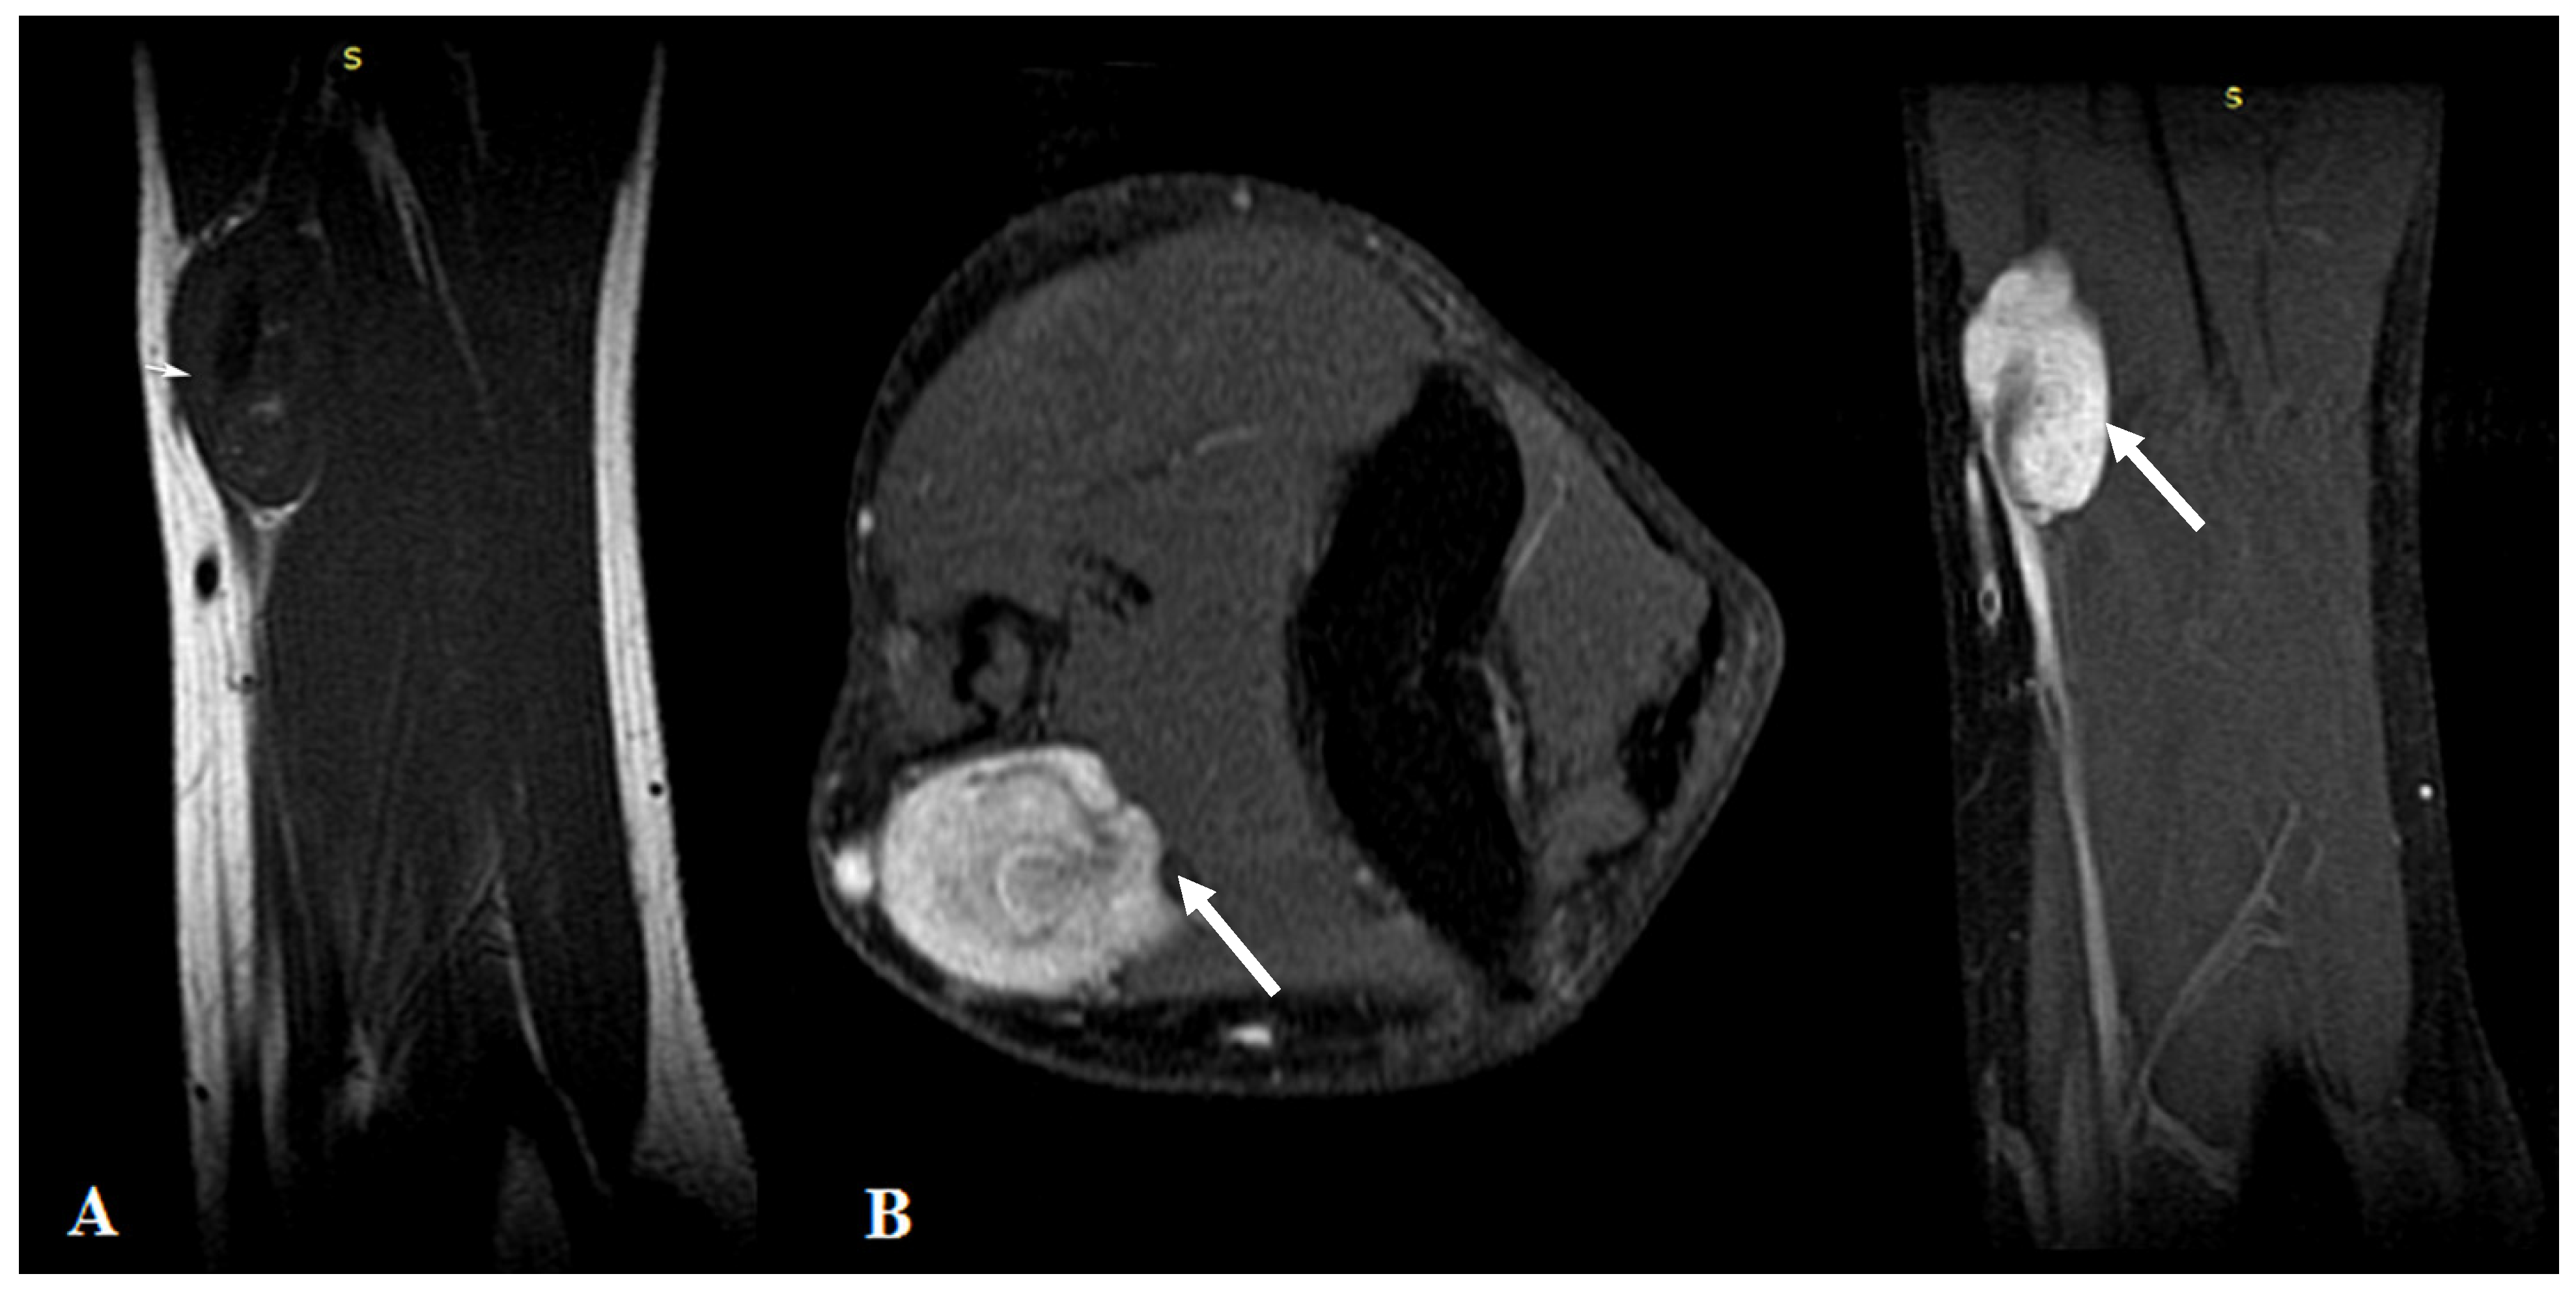

MRI highlighted the vascular origin of the mass, arising from the arterial wall, located above the brachial artery bifurcation, anteriorly to the right medial epicondyle. It was well delineated with circumscribed borders and had T2 hyperintense signal intensity (SI), T1 hypointense SI (Figure 1A) and avid, homogenous enhancement after contrast administration (Figure 1B). Small vessels were seen originating from the brachial artery with intratumoral distribution.

Figure 1.

(A): MRI imaging—T1WI Sagittal plane showed a homogeneous dark T1 signal of the mass (arrows). (B): Contrast-enhanced MRI imaging with fat saturation—axial and sagittal plane showed intense homogenous contrast enhancement of the tumor.